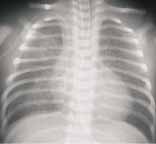

Las atelectasias aparecen como imágenes en cuña, densas, caracterizadas por signos de pérdida de volumen dados por desplazamiento de las cisuras, acercamiento costal, elevación del hemidiafragma y desplazamiento del mediastino y pueden ser segmentarias o subsegmentarias o comprometer todo un lóbulo (Figuras 3,4,5). Se han descrito más comunes en los tercios inferior y medio del pulmón4. La inadecuada interpretación de estas áreas de opacidad focal puede sugerir roceso neumónico.

FIGURA 4. Imagen típica de atelectasia parcial del hemitórax derecho, hay desplazamiento del corazón, mediastino, traquea y elevación del hemidiafragma correspondiente. |